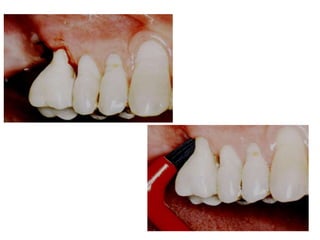

TRATAMENTO DAS LESÕES

ENDOPERIODONTAIS

Hemisseccção

DEL RIO, 1996